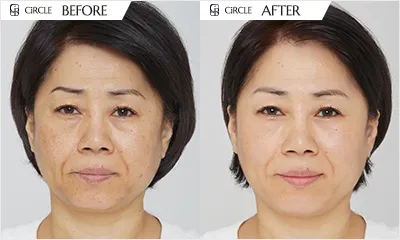

Scars

Pores